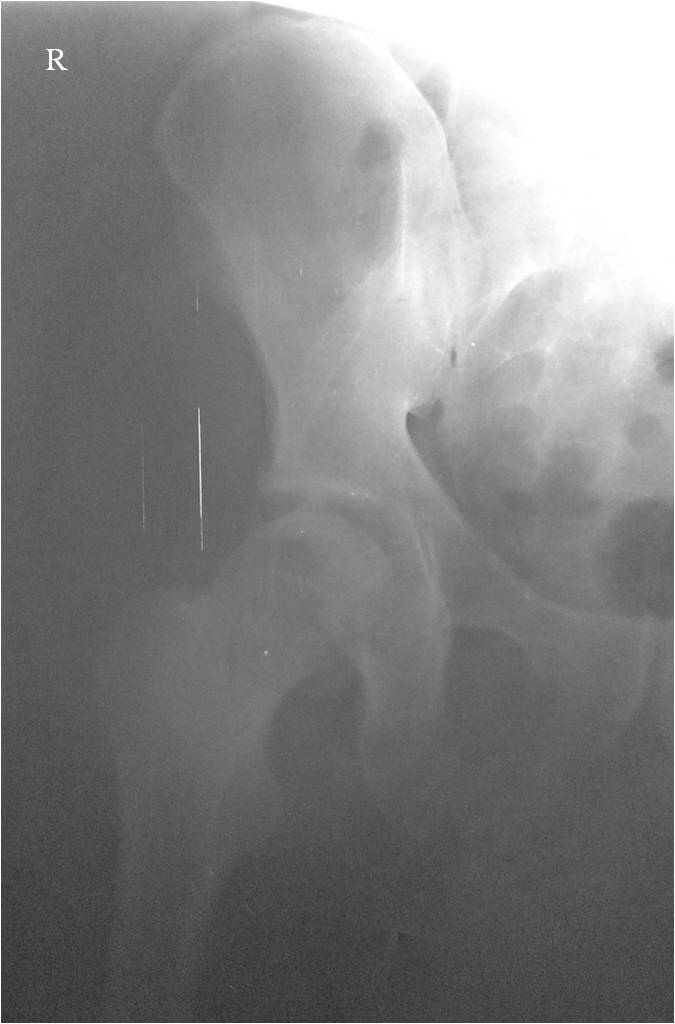

При поступлении выполнено закрытое вправление головки бедра, налажено

скелетное вытяжение. Контрольный рентген показал разницу в ширине

суставных щелей в сравнении с неповрежденной стороной. Сделали КТ,

которое подтвердило наличие внутрисуставного фрагмента задней стенки

вертлужной впадины и перелом нижне-медиального сегмента головки со

смещением (Pipkin IV).